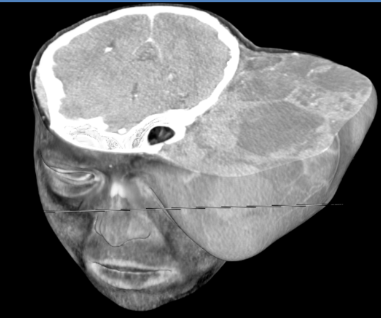

Computed tomography

Contrast-enhanced axial CT

- Soft tissue density mass, involving the superficial layers of the left hemiface, apparently originating from the cutaneous and subcutaneous tissues.

- The mass is composed of nodular material with heterogeneous attenuation. The nodules have hyperdense contours and predominantly hypodense internal contents with heterogeneous enhancement.

- Irregularity in the cranial skull with thinning and remodeling.

- There was no intracranial extension.